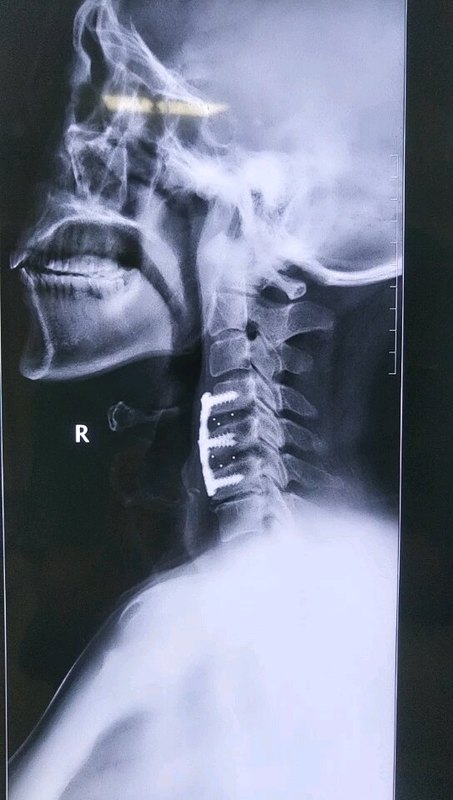

颈椎前路融合手术后注意事项

颈椎前路显微手术

颈椎前路手术

临床创新一:颈前路经椎间隙骨赘切除扩大减压融合内固定术

颈椎前路微创手术

颈椎术后康复锻炼方法(前路)

颈椎术后(前路)患者注意事项